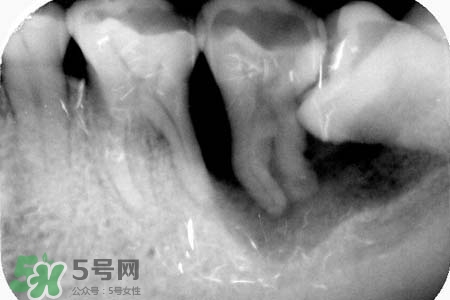

長智齒一般不會(huì)引起耳鳴,智齒冠周炎時(shí)可能會(huì)引起耳部放射性疼痛。耳鳴因素很多,若持續(xù)時(shí)間較長,因及時(shí)就醫(yī)。如果確定耳朵沒有問題,那么智齒導(dǎo)致的,癥狀是非??赡艿闹驱X阻生,應(yīng)盡早拔除,萌出空間不足、反復(fù)引起發(fā)炎也可考慮拔除。

耳鳴跟長智齒是沒有關(guān)系的。耳鳴建議多做耳部按摩,如:傳統(tǒng)的按摩方法鳴天鼓、雙手掌按住耳部,拇指置于腦后,四指敲打后腦勺。治療耳鳴可用擴(kuò)血管營養(yǎng)神經(jīng)類藥物,抗焦慮藥,抗抑郁藥,卡馬西平類抗驚厥類藥物,利多卡因及安定類藥物,以及六味地黃丸等中藥。